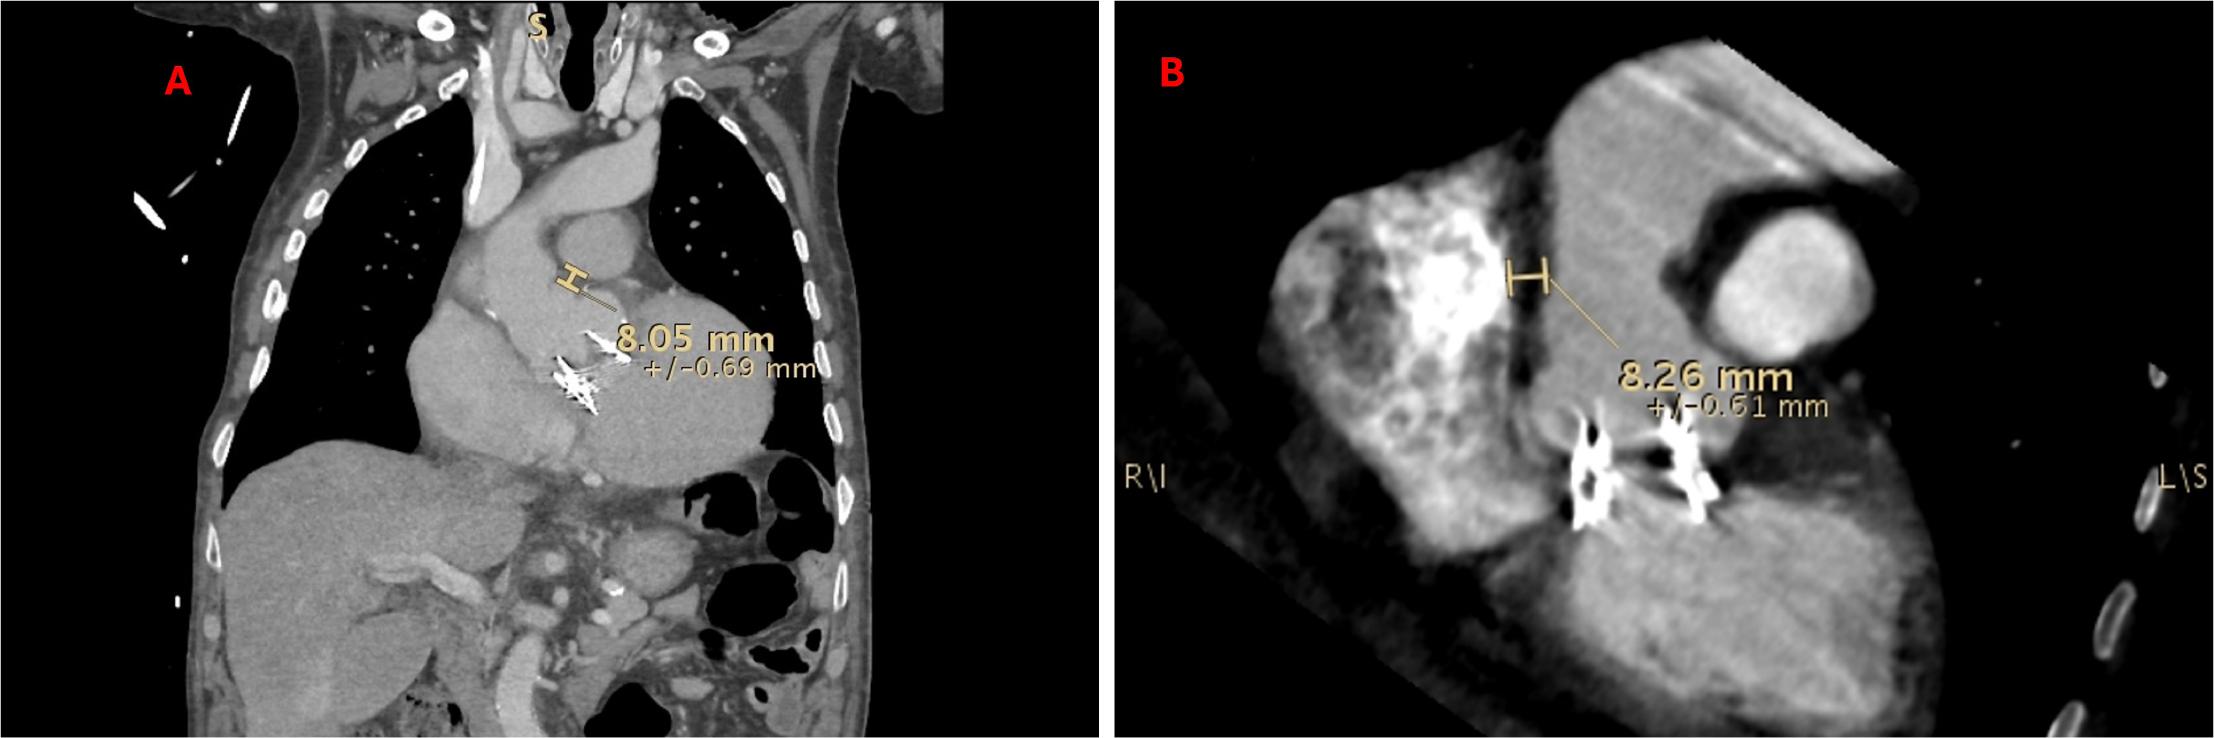

Figure 3